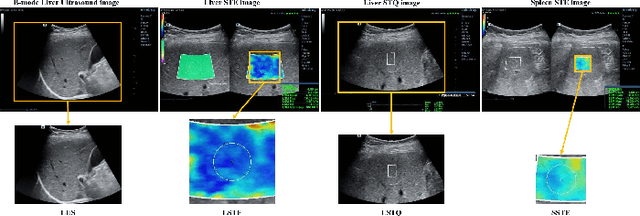

Abstract:With the development of radiomics, noninvasive diagnosis like ultrasound (US) imaging plays a very important role in automatic liver fibrosis diagnosis (ALFD). Due to the noisy data, expensive annotations of US images, the application of Artificial Intelligence (AI) assisting approaches encounters a bottleneck. Besides, the use of mono-modal US data limits the further improve of the classification results. In this work, we innovatively propose a multi-modal fusion network with active learning (MMFN-AL) for ALFD to exploit the information of multiple modalities, eliminate the noisy data and reduce the annotation cost. Four image modalities including US and three types of shear wave elastography (SWEs) are exploited. A new dataset containing these modalities from 214 candidates is well-collected and pre-processed, with the labels obtained from the liver biopsy results. Experimental results show that our proposed method outperforms the state-of-the-art performance using less than 30% data, and by using only around 80% data, the proposed fusion network achieves high AUC 89.27% and accuracy 70.59%.